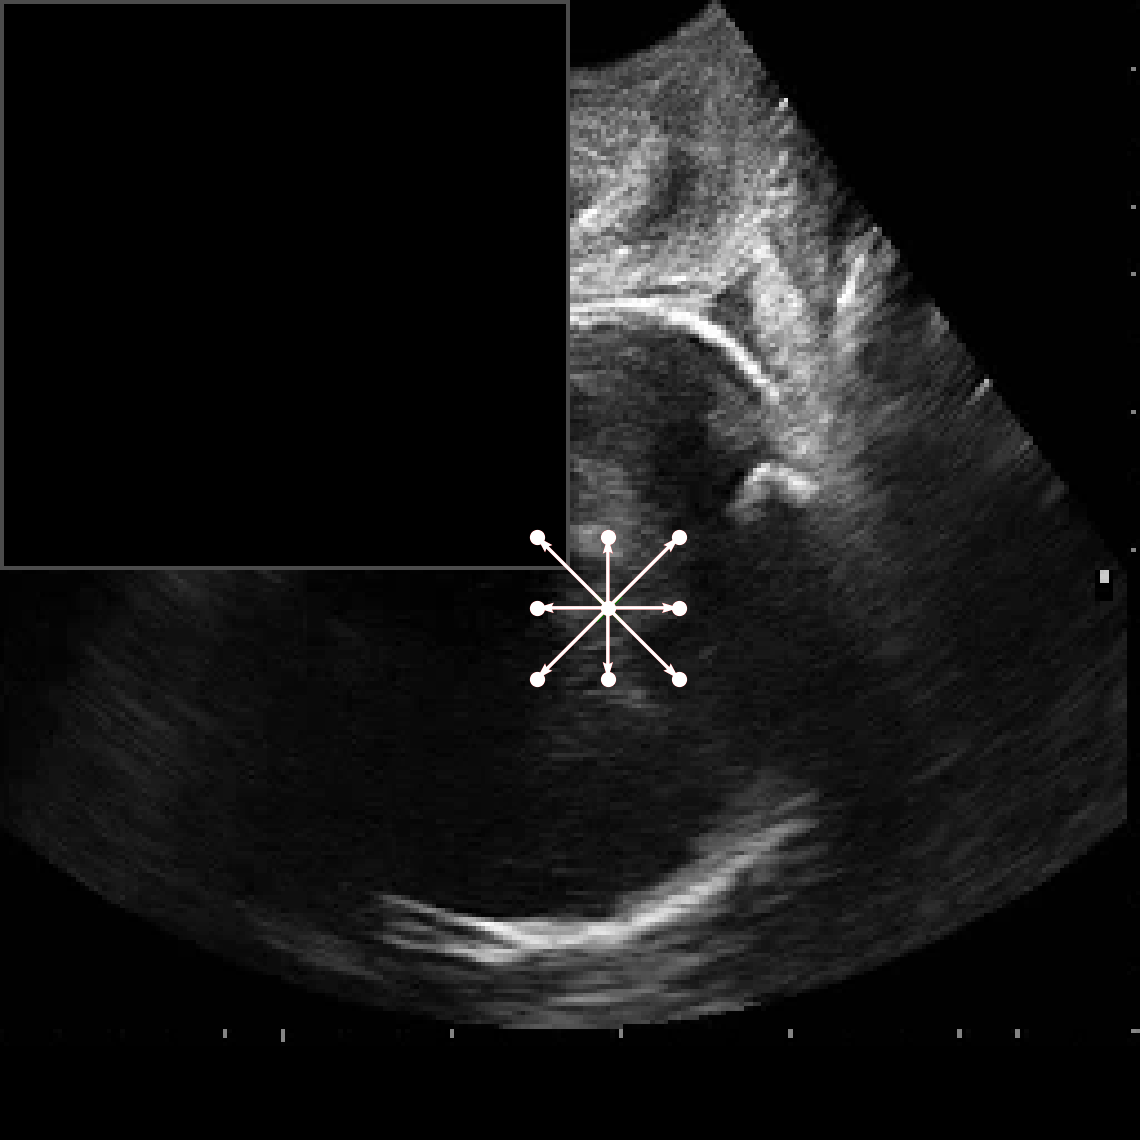

In practical clinical settings, medical images are often incomplete or degraded due to occlusions, artifacts, or limited fields-of-view. Therefore, a reliable segmentation model must be robust to missing spatial context and capable of inferring anatomical structures from partially observed inputs. To evaluate this critical property, we conducted a masking experiment using the FH-PS-AoP dataset. In this experiment, we systematically removed one quadrant from the input image, top-left, top-right, bottom-left, or bottom-right, and evaluated the performance of DAUNet compared to the baseline UNet.

Figure 7 presents a comprehensive visual comparison of the predicted offset maps and segmentation masks under each masking condition. The first column shows the original (unmasked) input along with its corresponding predictions, while subsequent columns depict the results for each of the masked quadrants.

DAUNet demonstrates markedly higher resilience to missing context compared to UNet. Its predicted offset maps remain dense and structured, with vectors that preserve anatomical directionality even when significant regions of the input are absent. This behavior reflects DAUNet’s ability to infer context from the remaining visual cues. In contrast, UNet exhibits sparse or disoriented offsets in the masked scenarios, indicating reduced spatial awareness and compromised localization.

To better understand this phenomenon, we analyzed the receptive fields of both models. For a representative pixel, we visualized its corresponding receptive area contributing to the output. In UNet, the receptive field is fixed and grid-constrained (refer to second row of Figure 7), making it sensitive to occlusions. On the other hand, DAUNet leverages deformable convolutions to dynamically adjust its receptive field based on the visible content. This adaptability is evident in the red and white arrows in the fourth column of Figure 7, where DAUNet modifies its offset patterns to account for the masked input.

The segmentation masks in third and fourth rows of Figure 7, further substantiate these findings. DAUNet consistently produces anatomically plausible segmentations of both the fetal head (green) and pubic symphysis (red), with minimal degradation even under 25% missing input. The output contours remain smooth, accurate, and well-aligned with ground truth boundaries. In contrast, UNet’s performance deteriorates noticeably, with fragmented or distorted segmentations, especially around the fetal head, as indicated by white arrows in the figure.

These results highlight the efficacy of DAUNet’s architectural innovations. The combination of deformable convolution and SimAM attention allows the model to effectively reason over the visible context and compensate for spatial omissions. This robustness to incomplete inputs makes DAUNet well-suited for deployment in real-world medical environments, where noise, occlusions, and partial data are common challenges.